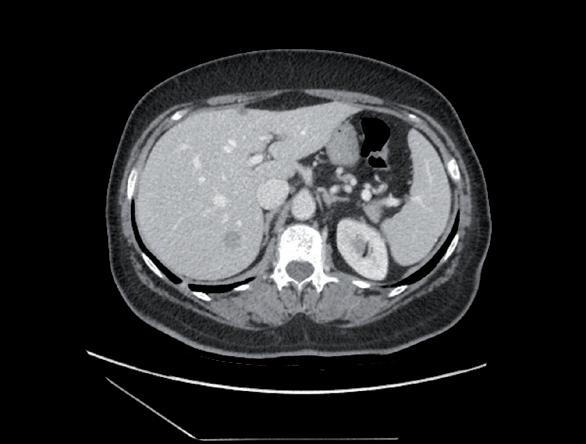

Con la PET/TC eseguita a novembre del 2016 si evidenziava la presenza di significative alterazioni di distribuzione del radiofarmaco a carico del fegato e a livello scheletrico, come da alterazioni di natura sostitutiva. In particolare, in corrispondenza del fegato, si segnalava significativa captazione focale a livello del settimo segmento e altra poco più cranialmente. Si evidenziavano poi plurime significative captazioni estese a tutto il rachide cervicale, dorsale e lombare (SuvMax fino a 18) oltre che a tutto il bacino, oltre che a livello delle coste bilateralmente, clavicola sx, manubrio sternale, entrambe le scapole, entrambe le teste e diafisi prossimali omerali, diafisi omerale destra, entrambi i femori a livello delle teste, delle regioni trocanteriche, maggiormente a sx, diafisi prossimali femorali, corrispettivo alle immagini TC ad alterazioni addensanti, in parte ad alterazioni litiche, in parte a malattia ancora in fase pre-radiologica (figura 1).

1. TC/PET TB, novembre 2016.

Figura